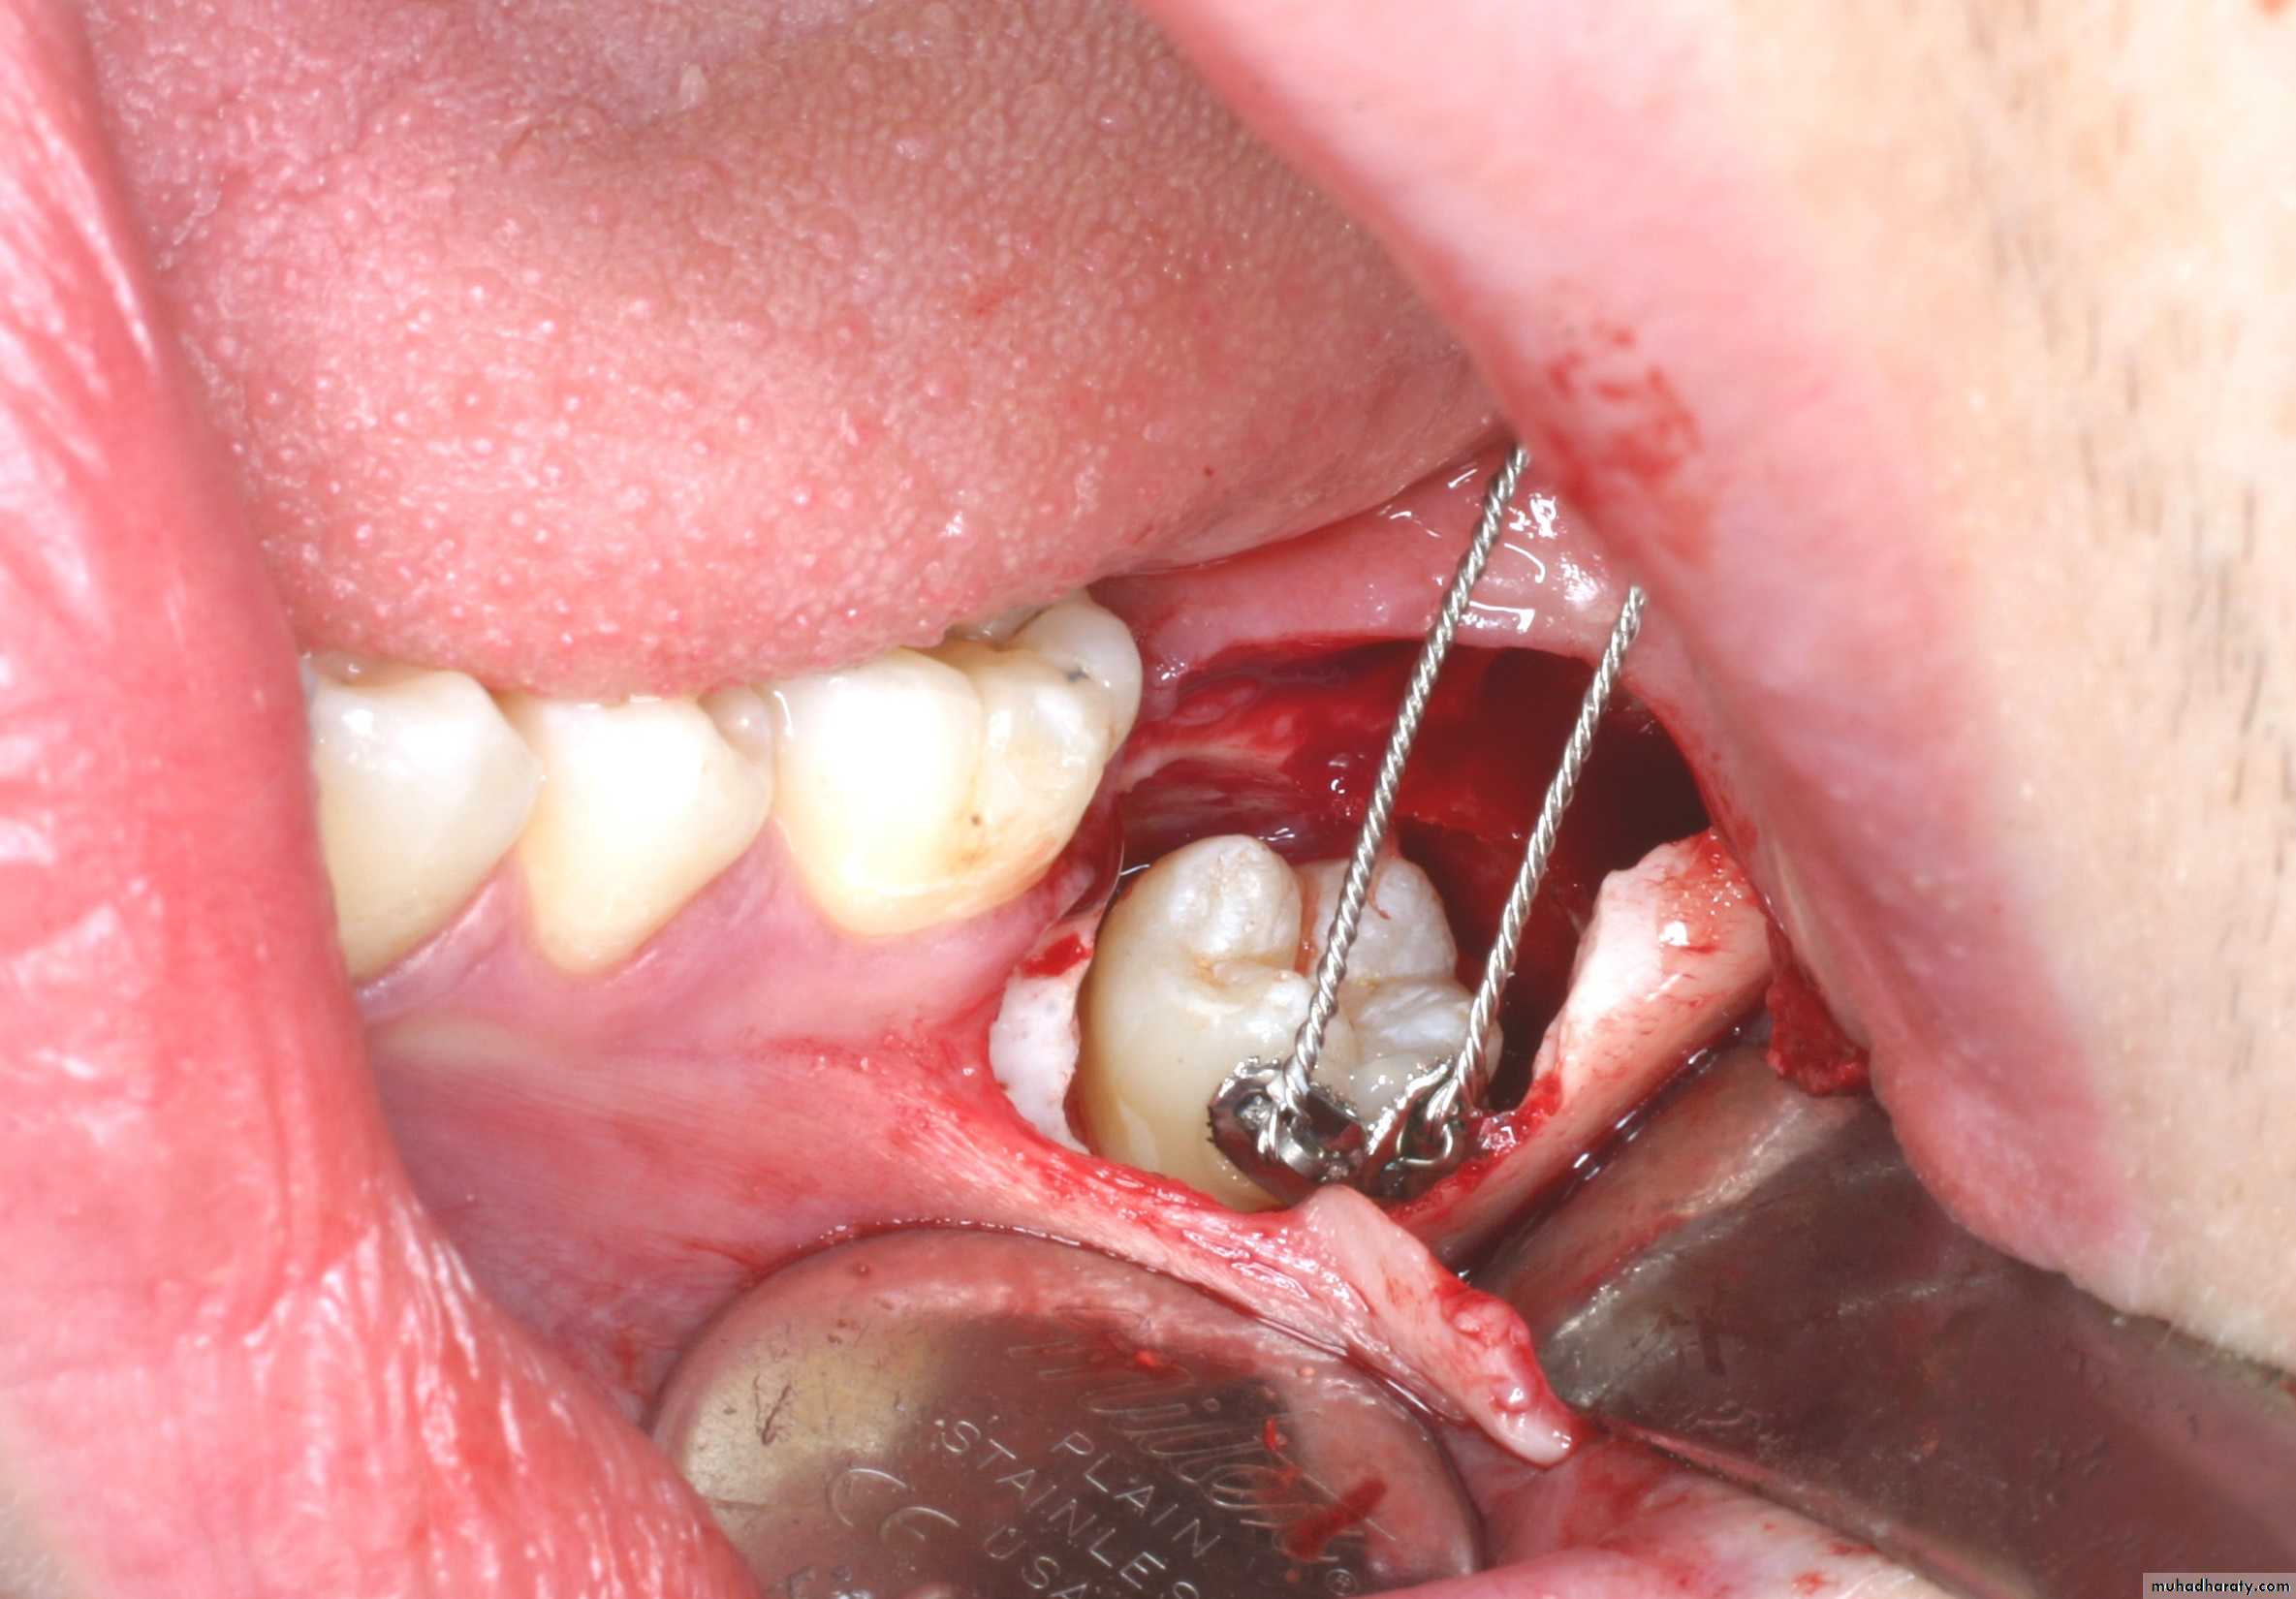

Another line of treatment is the surgical up-righting, especially of the impacted second molar. This is done through buccal approach, the tooth is exposed carefully without exposing the CEJ, if the third molar is present it needs to be removed, if not, bone posterior to the second molar is removed, followed by tipping the tooth slightly posteriorly and superiorly, and the tooth can be allowed to erupt spontaneously. This procedure is better carried out when 2/3 of the roots of the impacted second molar are developed. Teeth with fully developed roots have poor prognosis for this procedure

Usually there is no need for fixation but RCT may be needed 6-8 weeks after surgery, also there should be no occlusal forces on the tooth in the postoperative period. Follow up for about 2 years is necessary.